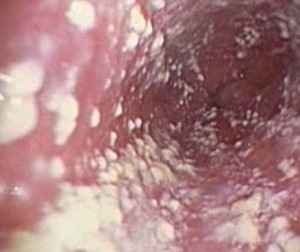

Что такое молочница кишечника и симптомы заболевания? Проявления кандидоза всегда предельно выражены и, обнаружить их достаточно просто. Когда инфекционное заболевание поразило тонкую кишку (см. фото) разглядеть его можно по фактуре испражнений, а по внешнему и внутреннему состоянию человека: